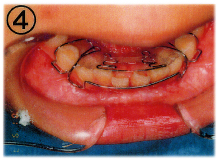

当医院では「床(しょう)矯正」という矯正治療を実践しております。

基本的には永久歯を抜かず、顎を拡げて歯を並べる治療の事です。

床矯正で使用する装置は簡単に取り外せるので、虫歯や歯周病を患いにくく、清潔な口腔環境が保てます。